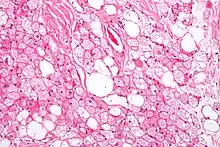

Hibernoma (intermediate magnification).

Hibernoma (intermediate magnification).

The tumors histologically resemble brown fat. There are four histologic types recognized, but one is the most frequently seen (typical). There is a background of rich vascularity.

- Lobular type: Variable degrees of differentiation of uniform, round to oval cells with granular eosinophilic cells with prominent borders, alternating with coarsely multivacuolated fat cells (pale cells). There are usually small centrally placed nuclei without pleomorphism. The cells have large cytoplasmic lipid droplets interspersed throughout.[3][4]